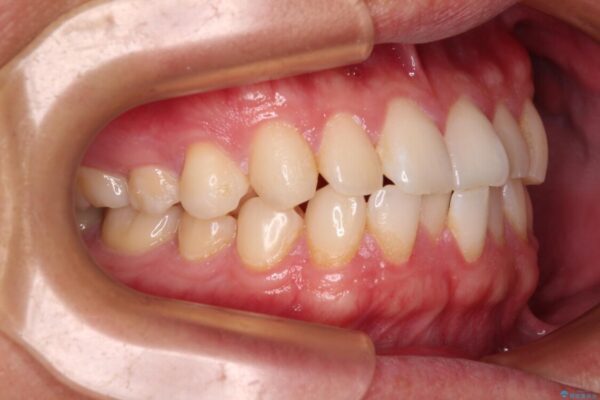

治療前

• 前歯のガタガタ・奥歯のかみ合わせ(シザーズバイト)を改善|1年半で完了したメタルブラケット矯正 治療前画像